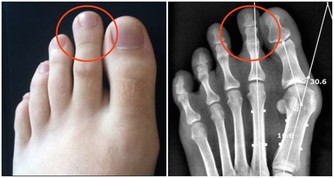

(圖片翻攝自華人健康網)